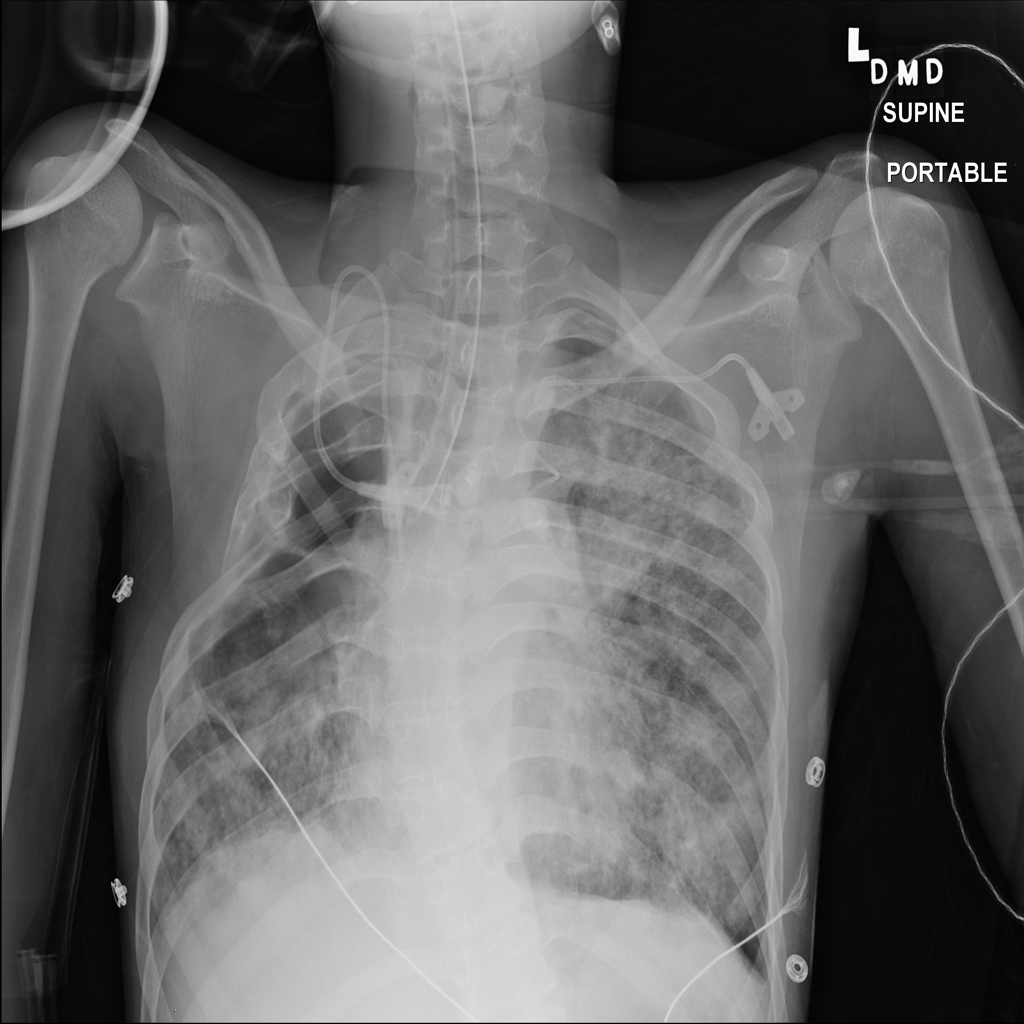

Pneumothorax representative X-ray

Reference image: PAT-EEB6 · IMG-029 · Bounding-box highlight from source annotation where available.

• On chest X-ray, pneumothorax may appear as pleural air with a visible visceral pleural line and relative absence of expected lung markings beyond that line

• Small pneumothoraces can be subtle, especially on portable or supine films

• Radiologists look for pleural air, the visible lung margin, degree of lung collapse, and whether there are signs of pressure effects such as mediastinal shift